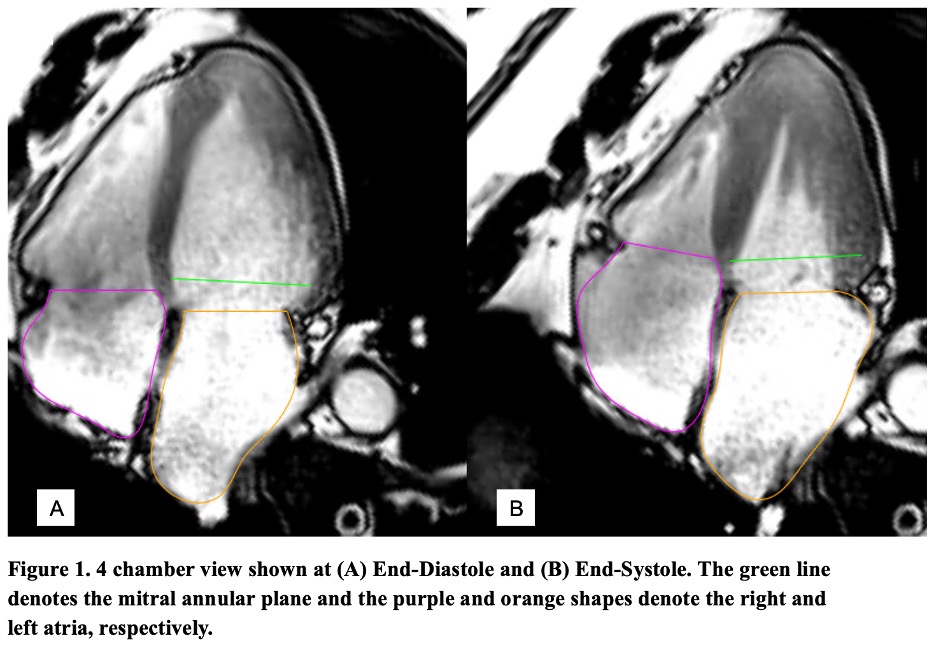

Table 1. Cardiac MRI and Transthoracic Echocardiographic Characteristics of Hypertrophic Cardiomyopathy Patients.